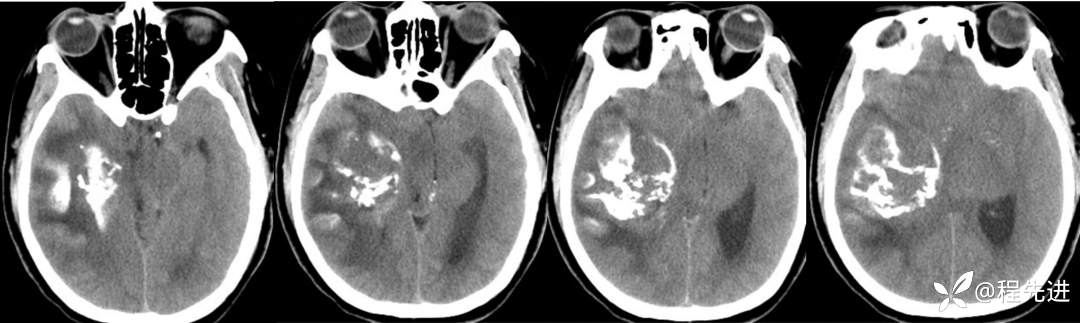

CT平扫: